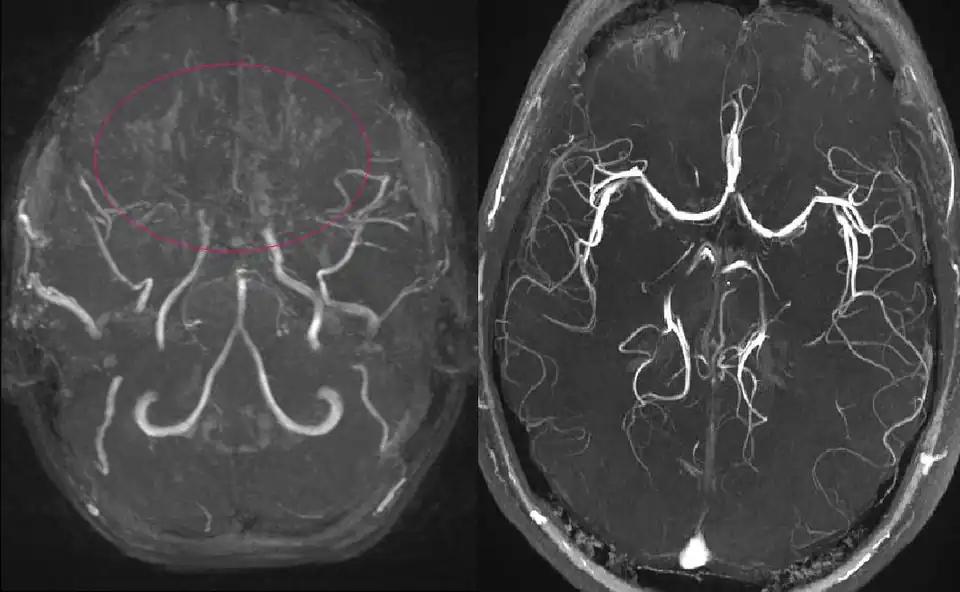

Ressonancia magnética de uma menina de 11 anos com Moyamoya

A angiografia por ressonância magnética (RM) e a angiografia por tomografia computorizada são métodos de diagnóstico não invasivos. As imagens de RM de alta resolução da parede do vaso também ajudam a diagnosticar a DMM, revelando um estreitamento concêntrico da parede do vaso com colaterais basais. A doença de Moyamoya (DMM), significa uma "nuvem de fumo" em japonês, também designada por oclusão espontânea do círculo de Willis, é uma doença cerebrovascular oclusiva crónica de etiologia desconhecida, caracterizada por alterações estenooclusivas na porção terminal da artéria carótida interna (ACI) e por uma rede vascular anormal na base do cérebro.[1] Tendo em conta o número crescente de doentes com envolvimento unilateral,[2] bem como a evidência de que um número substancial de casos unilaterais progride para uma apresentação bilateral,[3][4] os critérios de diagnóstico para a DMM definitiva foram revistos de modo a incluir doentes com apresentação bilateral e unilateral de estenose da ACI terminal com uma rede vascular anormal na base do cérebro (declaração do Comité de Investigação da DMM do Ministério da Saúde, Trabalho e Bem-Estar do Japão em 2015). Os critérios de diagnóstico também indicam que o diagnóstico definitivo da DMM requer uma angiografia por cateter nos casos unilaterais, ao passo que os casos bilaterais podem ser prontamente diagnosticados quer por angiografia por cateter quer por ressonância magnética/angiografia (RM/ARM). Quando há doenças causadoras ou condições associadas, termos como síndrome de moyamoya e moyamoya angiográfica são freqüentemente usados.[5] Embora incomum, a DMM é uma importante causa de doença arterial intracraniana não aterosclerótica, especialmente nos países do leste asiático. Nessas regiões, a estenose isolada da artéria cerebral média é observada em pacientes jovens, com eventual evolução para DMM.[6] A DMM é a causa mais importante de AVC ou ataque isquémico transitório (AIT) em crianças nesta parte do mundo.